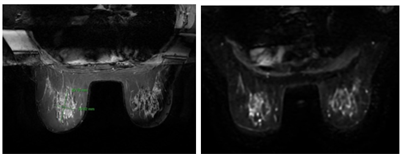

Case lâm sàng: Ứng dụng trí tuệ nhân tạo (Artificial intelligence – AI) trong chẩn đoán và điều trị sớm Ung thư phổi tại Trung tâm Y học hạt nhân và Ung bướu, Bệnh viện Bạch Mai

Theo GLOBOCAN 2022, ung thư phổi đứng đầu về số ca mới mắc (2.480.301 ca mới mắc chiểm 12.4%) và dẫn đầu số ca tử vong (1.817.172 ca tử vong chiếm 18.7%) trên toàn thế giới.  Tại Việt Nam tỷ lệ mắc ung thư phổi xếp thứ ba 13,5% lệ tử vong...